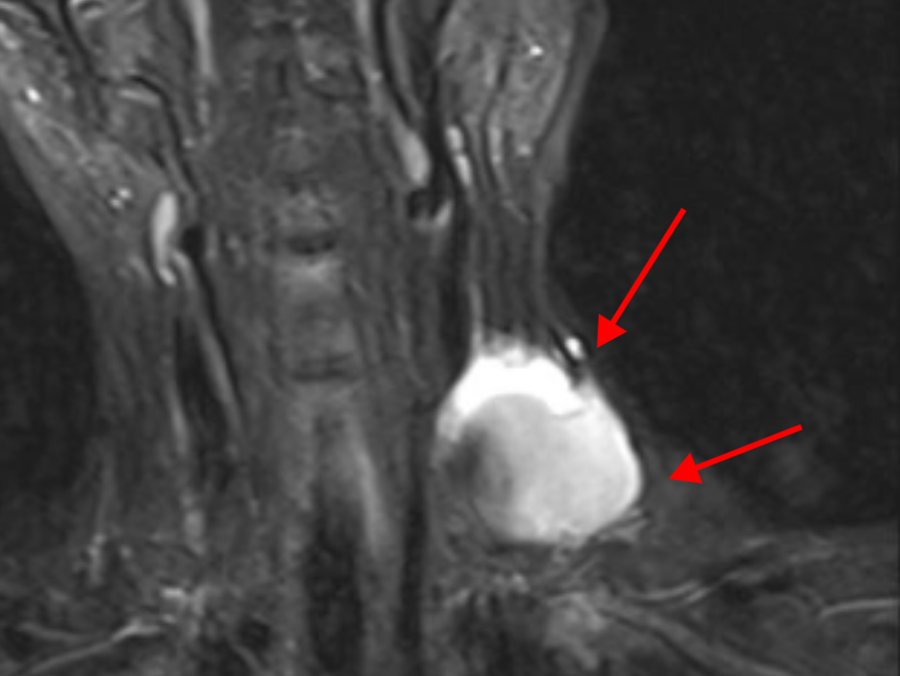

随后,吴女士被推入了手术室。在腹腔镜下,医生发现她的盆腔内已经有少量淡黄色腹水,而且盆腔已经发生了粘连,右侧盆壁大血管、神经和肌肉的后方形成一脓肿,里面充满了黄色浓稠的脓液,因为位置深,细菌极易入血引起感染性休克。